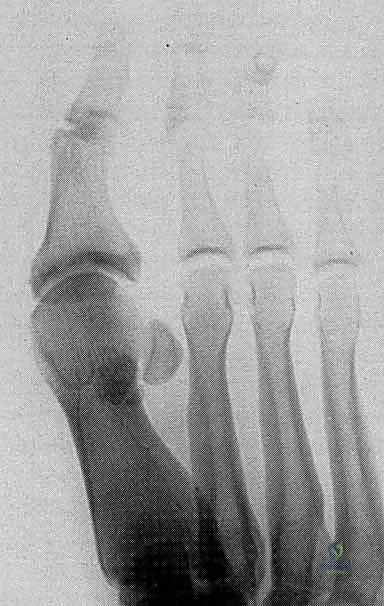

2. التصوير بالأشعة السينية (X-Rays)

يتم إجراء صور أشعة سينية بوضعيات تحمل الوزن (Weight-bearing) وبوضعيات الإجهاد (Stress views). تساعد الأشعة السينية في:

* استبعاد وجود كسور في عظام المشط أو السلاميات.

* تقييم العظام السمسمانية (البحث عن كسور أو هجرة غير طبيعية للعظام السمسمانية، مما يدل على تمزق الصفيحة).

* تقييم تضيق المسافة المفصلية.